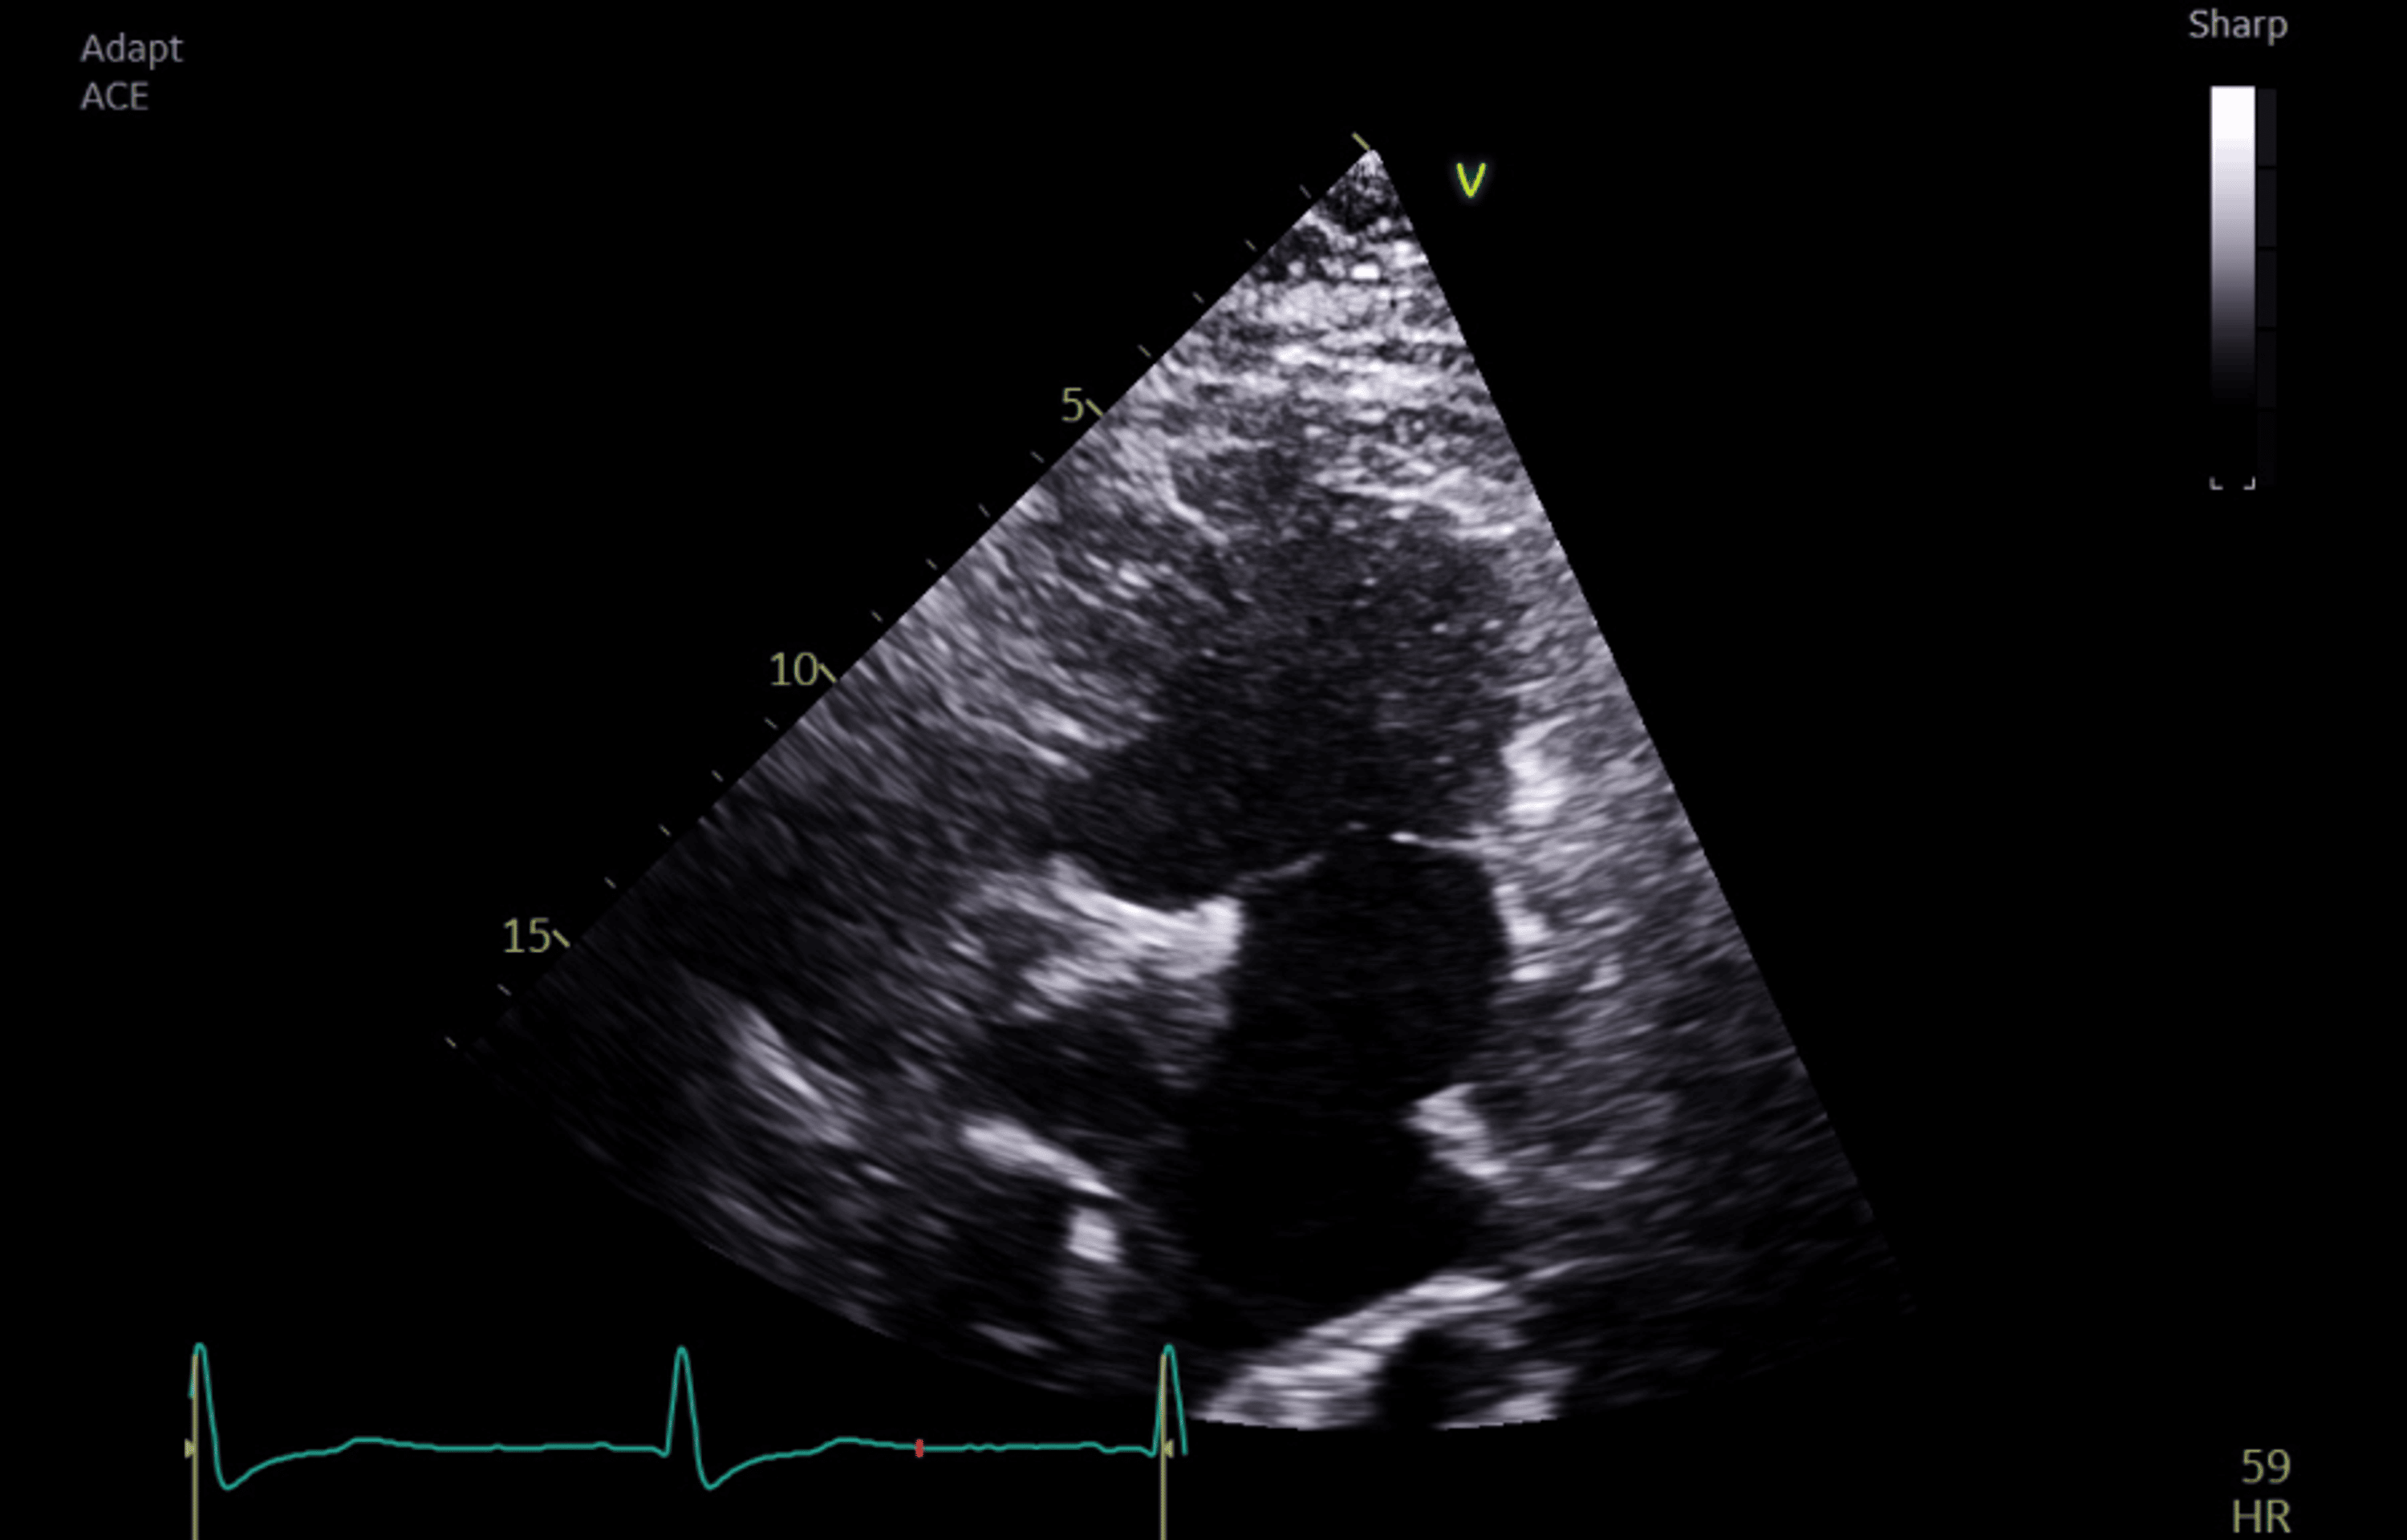

Intraoperative TOE showed good systemic ventricular function and left atrioventricular valve regurgitation. The total cavopulmonary connection (TCPC) demonstrated laminar flow in both caval pathways, with blunting and cessation of forward flow during positive pressure inspiration (Figures 1–2).